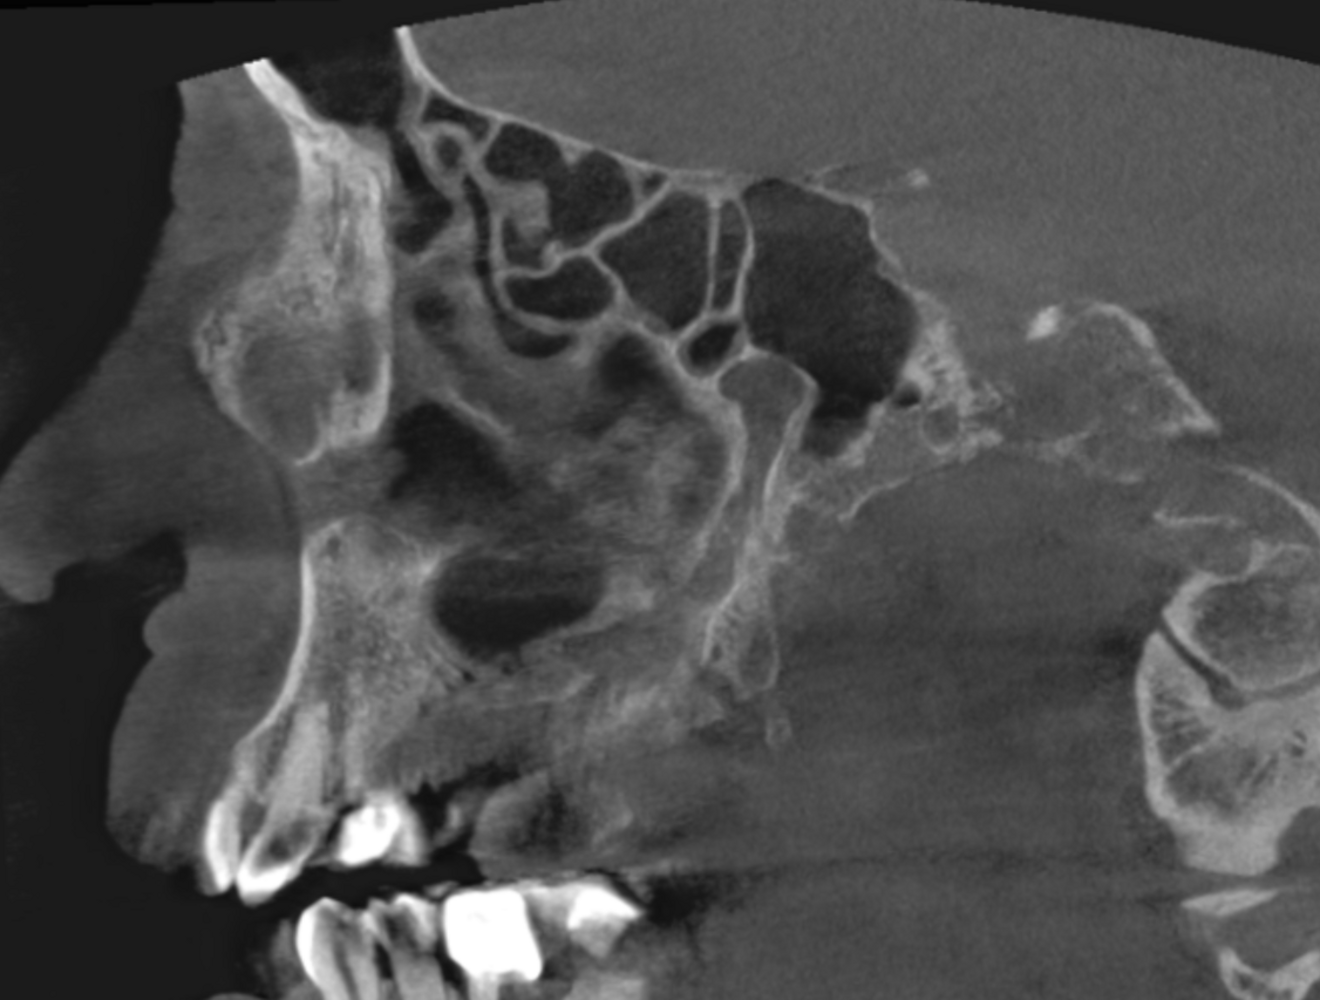

Fig. 4: Large-volume CBCT scan, sagittal cross-section of the right paranasal sinuses showing involvement of even the lower part of the cavernous sinus.

The extent of the inflammation was shocking (Figs. 2a & b). Not only the maxillary sinus (Fig. 3) but the ethmoid and sphenoid sinuses too were involved, and the inflammation had spread towards the right cavernous sinus as well (Fig. 4). At this point, extraction may have been the first choice for most dental clinicians, but we had to keep in mind that invasive treatment may have increased the risk of cavernous sinus thrombosis, a potentially avoidable possibility. There are very few circumstances under which a dental procedure can cause very severe or even lethal consequences, but this case approached such a situation.